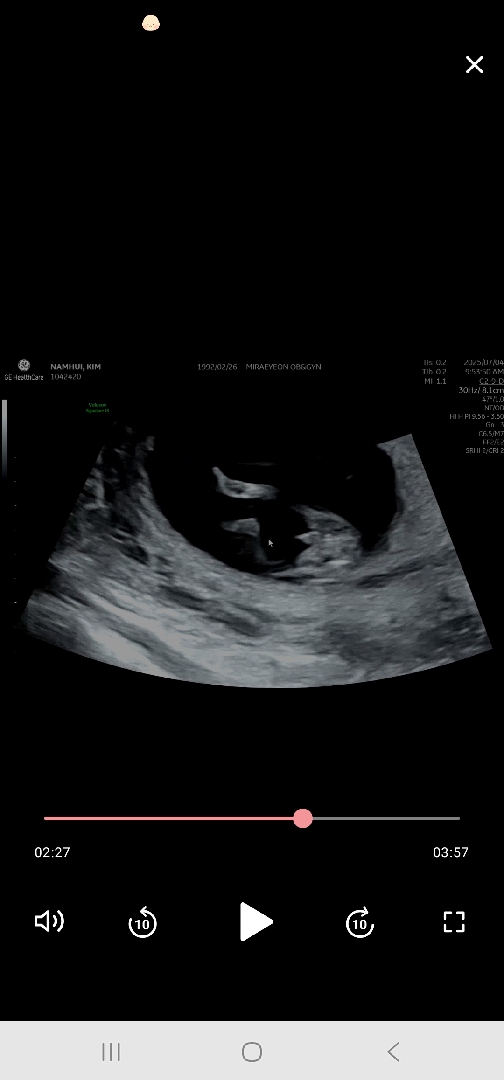

빼박 아들이겠죠 12주 초음파

너무 선명하다고들 하셔서

😆빼박 아들이죠 ..

존재감 확실한거 같죠 ...건강하다는거죠 ㅎㅎㅎㅎ .... 딸을 많아 원했어서 실망감도 크네요